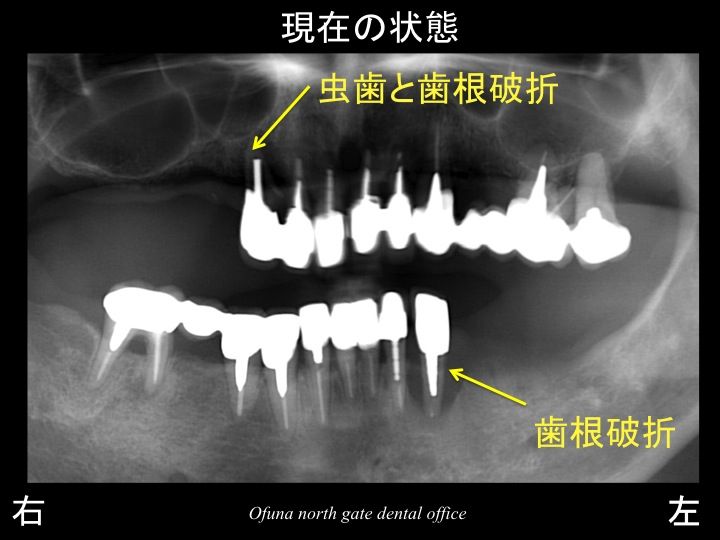

先にも説明しましたように現在の状況に戻りますが、

上顎の右側は、虫歯 と歯根破折 、

下顎左側は歯根破折 を起こしていました。

この2歯は抜歯になります。

それぞれの部位を拡大して見てみましょう!

まず、上顎右側です。

黄色丸の部分を拡大したのが以下のレントゲンになります。

右側(レントゲン写真なので反転してあります。図で右と書いてある方です)は、歯根破折 しています。

しかし、他にも問題がありました。

右側から2番目と3番目は、虫歯が大きく進行している状態でした。

左側は根の先に膿みが溜まっている状態です。

次に下顎左側です。

この黄色丸部分を拡大してみましょう!

レントゲン上で黒っぽくなっている部分は、

歯根破折 により感染したことによって、

歯の周囲の骨が吸収(溶けてしまった)したのです。

本当は、これほど骨吸収を起こす前に抜歯が必要なのです。

骨吸収を起こすと 抜歯した後の治療が大変になるのです。